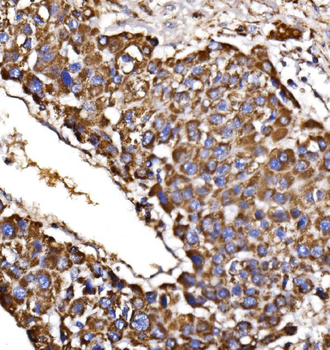

100 μl, 50 μl, 200 μl - HSC70 Mouse Monoclonal Antibody [orb704174]Featured

IF, IHC-Fr, IHC-P, WB

Human, Mouse, Rat

Mouse

Monoclonal

Unconjugated

100 μl, 50 μl, 200 μl - ATF4 Recombinant Rabbit Monoclonal Antibody [orb704304]Featured